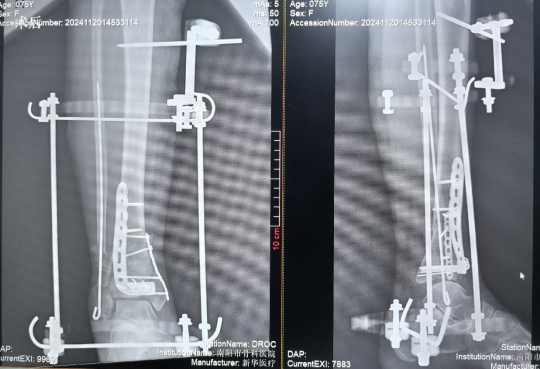

患者,女,75歲,主訴:踝部疼痛、腫脹,活動受限5天余。查體:右踝部畸形、腫脹明顯,局部按壓可觸及異常活動及骨擦感,踝關節活動明顯受限,足背動脈搏動可,足趾末梢血運及感覺尚可。診斷為右Pilon骨折見(Ruedi-Allgower III型)。

1.CO外固定半環連接跟骨穿針并通過CO接骨機器人配套的連接桿與CO接骨器人中間機械臂相連,調整機械臂,進行骨折端初步復位,C臂確認復位滿意,關節間隙拉開。

2.CO接骨機器人持續牽引維持復位,選擇前外側切口對前外側骨塊進行撬撥復位,并用克氏針進行臨時固定。C臂透視復位滿意,放置兩塊鋼板進行固定。

3.在脛骨近端穿入一根克氏針,連接CO外固定架進行固定,并外踝處穿入一根克氏針進行固定。C臂透視位置滿意,縫合結束手術。